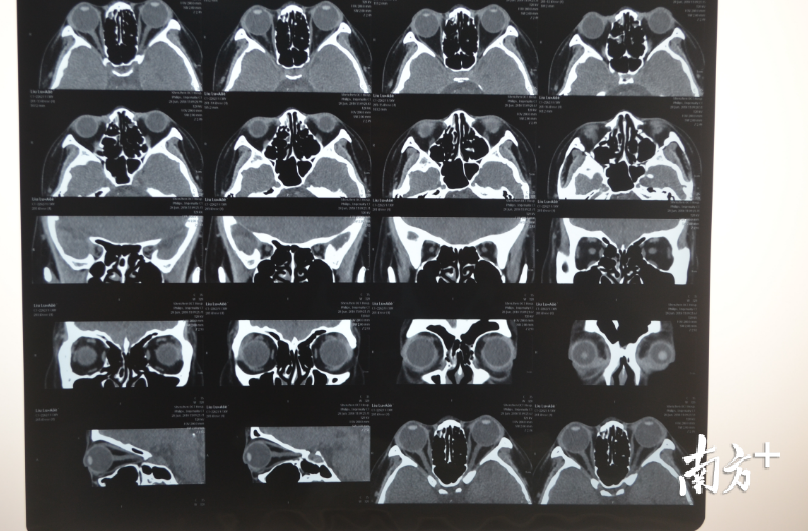

刘桂琴介绍,高度近视者之所以会感觉眼球突出,并不是眼球的位置发生了变化,主要是眼球变长了。“正常眼球接近圆球形,高度近视的人用眼过度后,眼球周边肌肉会变紧张,压迫眼球,导致眼球前后轴变长,就会出现眼睛变形,眼球前面就会突出来,像个‘金鱼眼’。”刘桂琴说,眼球的变长也是通过B超、CT或MRI检查出来的,患者自己感觉不到眼球变长,只感觉到眼球向前鼓出来了。

近日,刘桂琴就为刘洋实施了鼻内镜下经筛径路眼眶内壁减压术联合脂肪减压术,矫正其眼球突出。通过3个多小时手术,切除其眼球后面一部分眼球,给眼眶减压扩大其空间,让眼球能进去一些,减少了“突出”。据悉,这也是全球首例治疗高度近视眼球突出的无创手术。